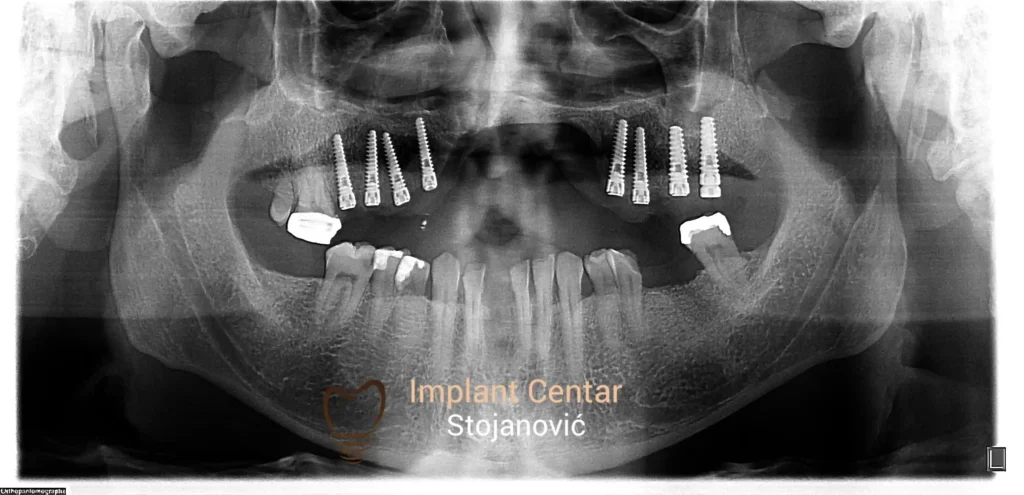

Zbog toga je plan terapije uključivao vađenje svih preostalih zuba i ugradnju implantata u gornjoj i donjoj vilici. U gornjoj vilici postavljena su i dva tuberopterigoidna implantata, kao zamena za sinus lift proceduru, što se može videti na ortopan snimku nurađenom odmah nakon ugradnje (slika 3).

Nakon vađenja zuba, ugrađeni su implantati. Na slici 3 prikazan je ortopan snimak sa ugrđenim implantatima. Tokom perioda osteointegracije, pacijent je bio zbrinut fiksnim privremenim krunicama na implantatima, koje su izrađene samo dva dana nakon hirurške intervencije.